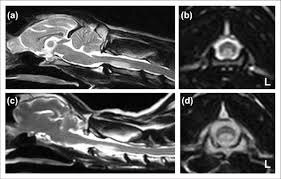

Ишемический инфаркт (типичный “паттерн”)

У кошек с предполагаемым острым инфарктом описаны очаги T1 iso/гипоинтенсивные и T2 гиперинтенсивные, иногда с мягким контраст‑усилением; при отсутствии другой системной патологии FCE рассматривается как вероятная этиология.

Для собак детально описаны МР‑находки у пациентов с предполагаемыми инфарктами/ишемической миелопатией и FCEM.

Важно: “нормальная МРТ” не исключает FCEM в первые сутки

Классическое клиническое знание, отражённое в обзорах, — МР‑изменения при FCE/FCEM могут быть минимальными или неочевидными в самые ранние сроки, что и объясняет интерес к DWI.